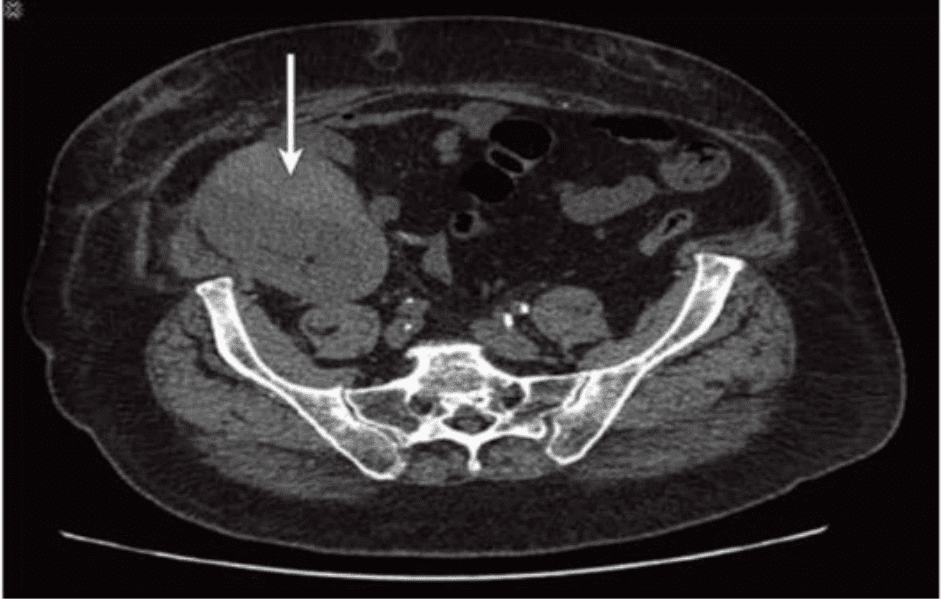

Which condition of the transplant kidney is indicated by the arrows on these images?